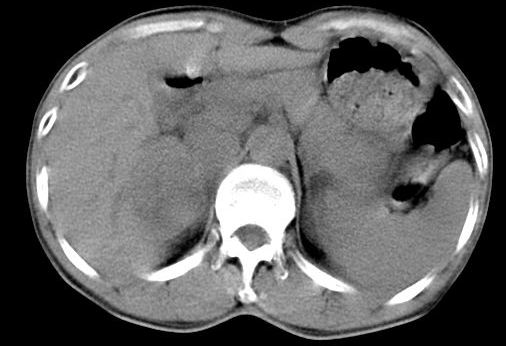

病人资料:男,50岁,上腹部隐痛,消瘦乏力,有乙肝病史二十余年,b超提示肝内内占位。

由于是基层医院,机器速度跟不上,增强效果差,请各位老师也看看!

肝右叶后下内侧段占位:肝癌可能性大

肝右叶后段低密度灶,增强受机器限制,特点不明显,无等密度充填及周围强化,结合病人乙肝史20年,首先考虑肝癌。

肝右后叶占位,增强时期没抓好,特点不明显,结合病史首先考虑原发性肝癌

肝右叶后下内侧段占位:肝癌可能性大。胰腺占位可能,病人没有空腹准备。

肝右叶后段占位,肝癌可能性大。下腔静脉无移位。肾上腺占位不支持?